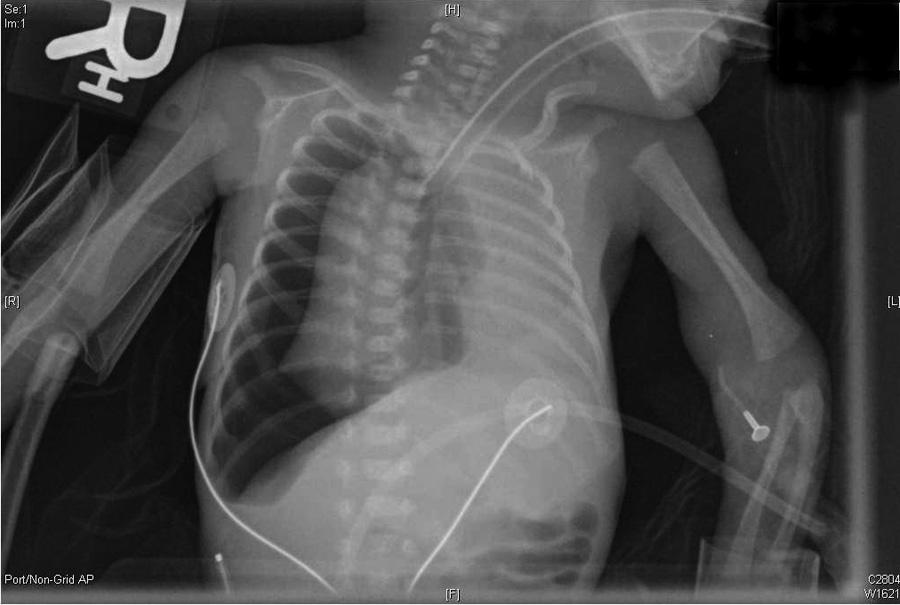

Neonate with a right tension pneumothorax. Note the tracheal deviation to the left.

Subcutaneous Emphysema and Pneumothorax